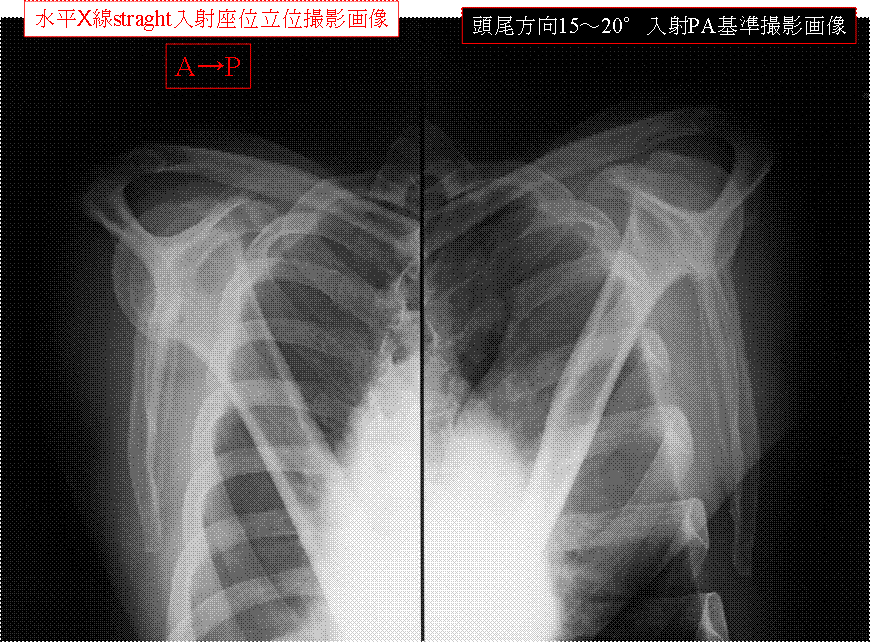

X線straight水平入射 座位立位AP撮影法 仰臥位AP撮影法 “肩部Yview画像”基準PA撮影法